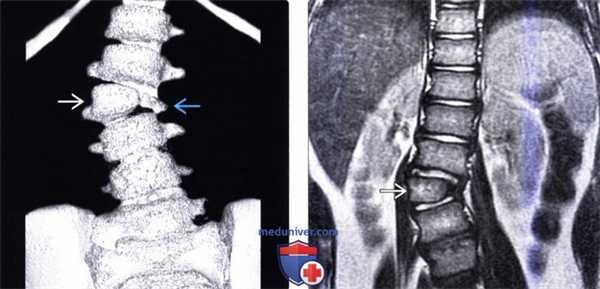

(Слева) На фронтальной схеме грудопоясничного отдела позвоночника показано многоуровневое нарушение сегментации позвонков, являющееся причиной врожденной сколиотической деформации позвоночника. Пространства между диспластичными позвонками заполнены хрящевой тканью и измененным веществом межпозвонковых дисков.

(Справа) На этом фронтальном КТ-срезе (врожденный сколиоз) приведен пример множественного нарушения сегментации позвонков с несколькими не полностью сегментированными правосторонними полупозвонками, формирующими причудливую картину и несколько дуг искривления. (Слева) Фронтальная трехмерная КТ-реконструкция: сколиотическая деформация позвоночника, характеризующаяся наличием правосторонней грудной и левосторонней грудопоясничной ки-фосколиотических дуг искривления, образующихся на фоне многоуровневого нарушения сегментации позвонков. Трехмерная визуализиация является наиболее оптимальным методом, позволяющим максимально оценить вклад тех или иных аномалий развития позвонков в формирование деформации позвоночника и выбрать исходя из этого наиболее оптимальный способ коррекции.

(Справа) Сагиттальная трехмерная КТ-реконструкция: фокальная кифотическая деформация позвоночника на уровне грудопоясничного перехода, связанная с многоуровневым нарушением сегментации позвонков.

(Слева) Трехмерная КТ-реконструкция: несбалансированный правосторонний L3 полу позвонок, являющийся в данном случае причиной правосторонней сколиотической деформации. Корень дуги и задние элементы L3 позвонка слева в данном случае представлены рудиментарными фрагментами.

(Справа) На фронтальном Т2-ВИ грудопоясничного отдела позвоночника у пациента со сколиозом обнаружен сегментированный несбалансированный правосторонний L3 полупозвонок. Такая односторонняя несбалансированная конфигурация у данного пациента стала причиной врожденной сколиотической деформации.